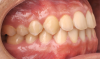

Fig 4. Pretreatment dental views of the patient; right lateral view (Fig 3), frontal view (Fig 4), and left lateral view (Fig 5).

Figure 4